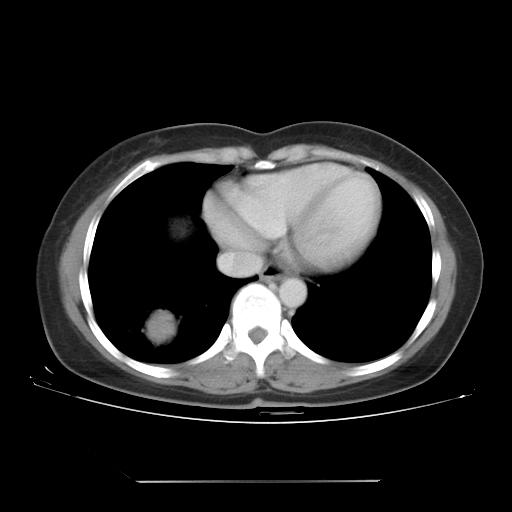

右肺下叶类癌

女 46岁,咳嗽咳血10月

【linyiming】右肺下叶见类圆形软组织影,边缘欠规整,略分叶状。考虑炎症假瘤可能?

未排除周围型肺癌。建议CT增强。

【心路寻觅】右肺下叶良性占位伴阻塞性肺炎,抗炎治疗后复查,不像单纯的炎性假瘤。

【刚起步】只有想不到的,没有长不到的。实性结节,强化明显,病人咳血,肺癌不能除外。

【aosangwa】肺癌的主要特征是:毛刺征、分叶征及胸膜凹陷征,此病例位于右肺下叶距胸膜很近,但没有胸膜凹陷征,其周围像示渗出性病变,病灶在两窗上没有大小没有发生大小改变。

考虑其良性肿瘤,炎性假瘤可能性大,其主要鉴别是:结核球、周围型肺癌、血管瘤

病理诊断类癌(周围型)。